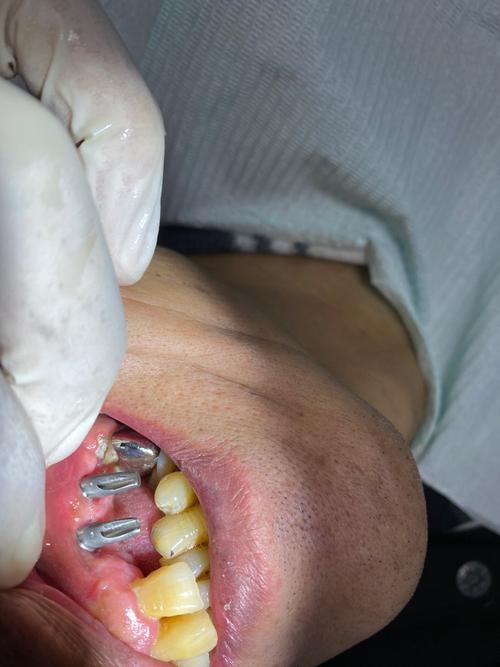

种植体松动或脱落

这是最直接的迹象,正常种植牙在咀嚼时应稳固无晃动,若用手轻摇种植牙或牙冠时感到明显松动,甚至种植体部分脱出,提示骨结合失败或机械性松动。

牙龈异常表现

种植体周围牙龈红肿、出血、溢脓,或牙龈萎缩、种植体“露头”,常是种植体周围炎的表现,炎症未及时控制会破坏骨组织,导致失败。